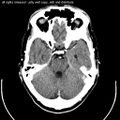

To identify cerebellar problems, neurological examination includes assessment of gait (a broad-based gait being indicative of ataxia), finger-pointing tests and assessment of posture.[4] If cerebellar dysfunction is indicated, a magnetic resonance imaging scan can be used to obtain a detailed picture of any structural alterations that may exist.[12]

Computed tomography of head, with cerebellum visible at lower part